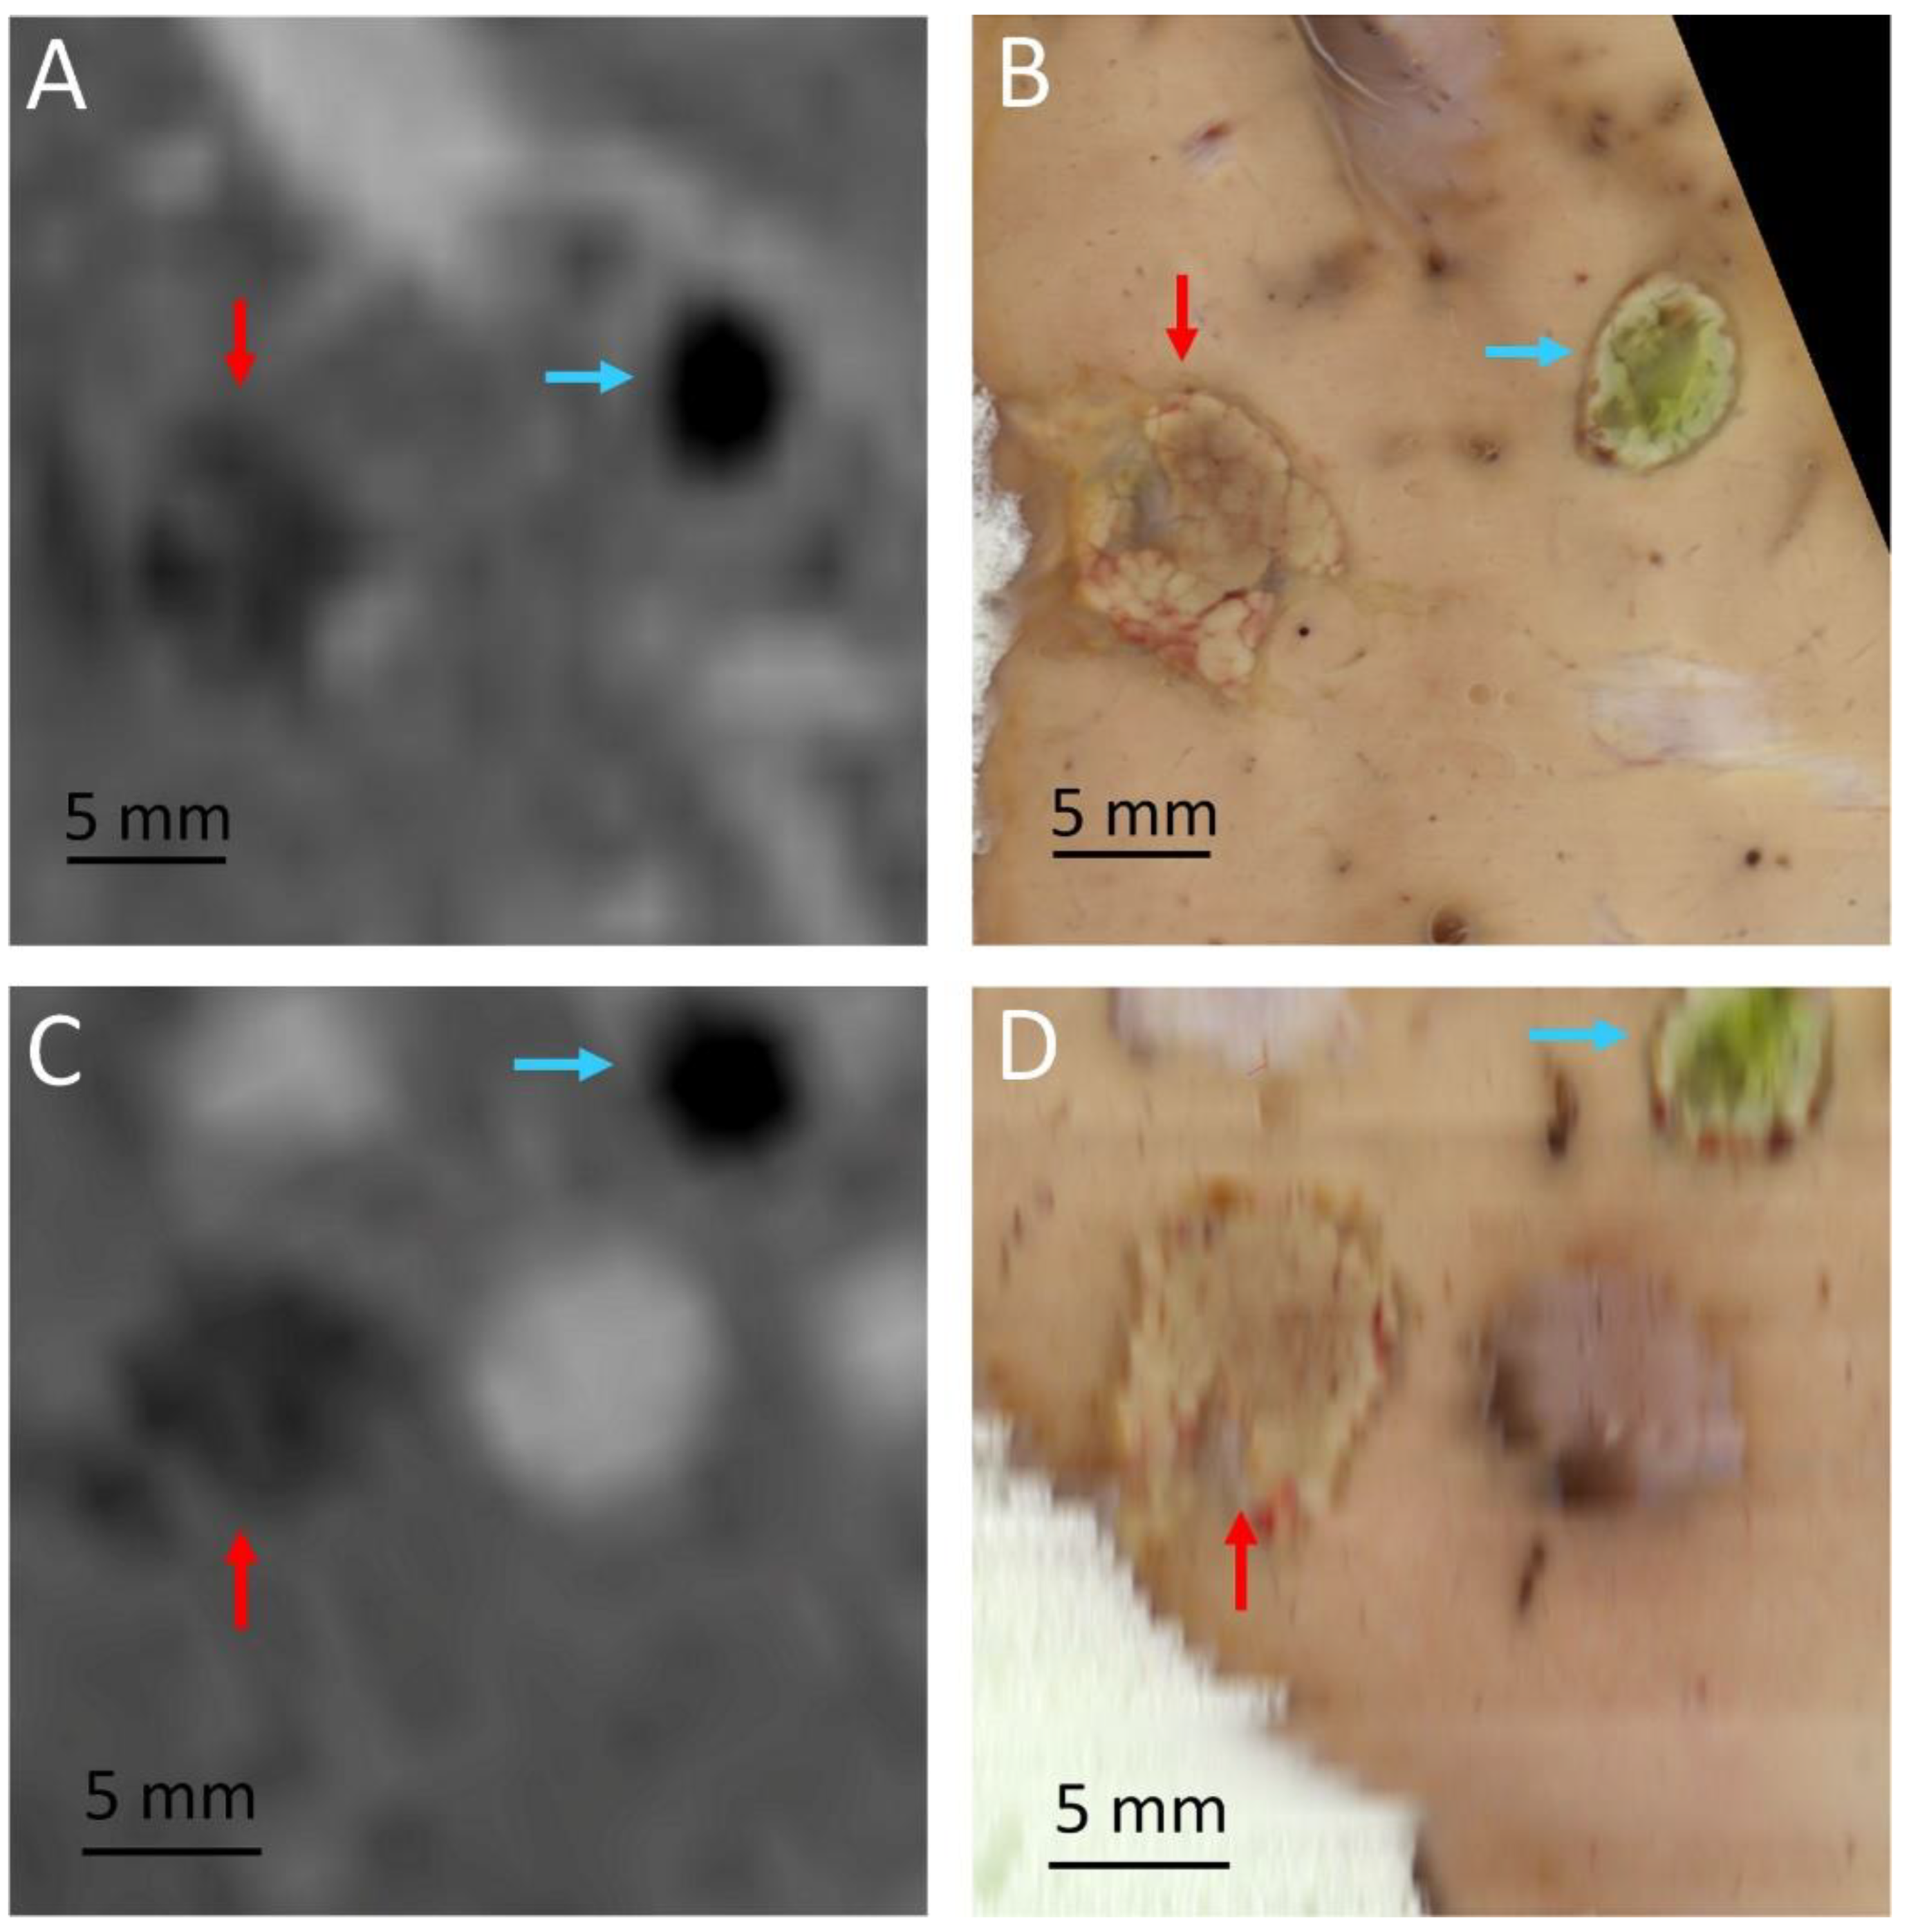

| Pig | RF Ablation Size (mm3), from MR Images (along AP, LR and HF Axes) | Temperature Reached During HIFU Ablation (°C) | HIFU Ablation Longest Axis (mm) from MR Images; See Figure 6 and Figure 7 | HIFU Ablation Longest Axis (mm), from Gross Pathology; See Figure 6 and Figure 7 | Planned Center-to-Center Distance between the RF and MRgHIFU Ablations (mm), from MR Images | Center-to-Center Distance between the RF and MRgHIFU Ablations (mm), from Gross Pathology | Center-to-Center Distance between the RF and MRgHIFU Ablations (mm), from MR Images | Near-Field Side Effects Grade |

|---|---|---|---|---|---|---|---|---|

| 1 | 4.9 × 6.1 × 4.8 | 63 | - | - | 0 | - | - | 1a |

| 2 | 7.2 × 6.3 × 9.2 | 86 | 6.9 | - | 11.8 | - | 10.1 | 1a |

| 3 | 4.6 × 3.7 × 4.5 | 85 | 15.8 | 16.5 | 6.7 | 3.6 | 3.2 | 1a |

| 4 | 6.7 × 6.1 × 6.8 | 86 | 7.4 | 7.9 | 16.1 | 16.0 | 16.2 | 1a |

| 5 | 5.1 × 4.7 × 6.2 | 62 | 21.1 | 23.2 | 18.4 | 24.2 | 24.1 | 1a |

| 6 | 3.0 × 4.6 × 5.5 | 58 | 14.0 | 15.0 | 11.2 | 10.3 | 10.3 | 1b |